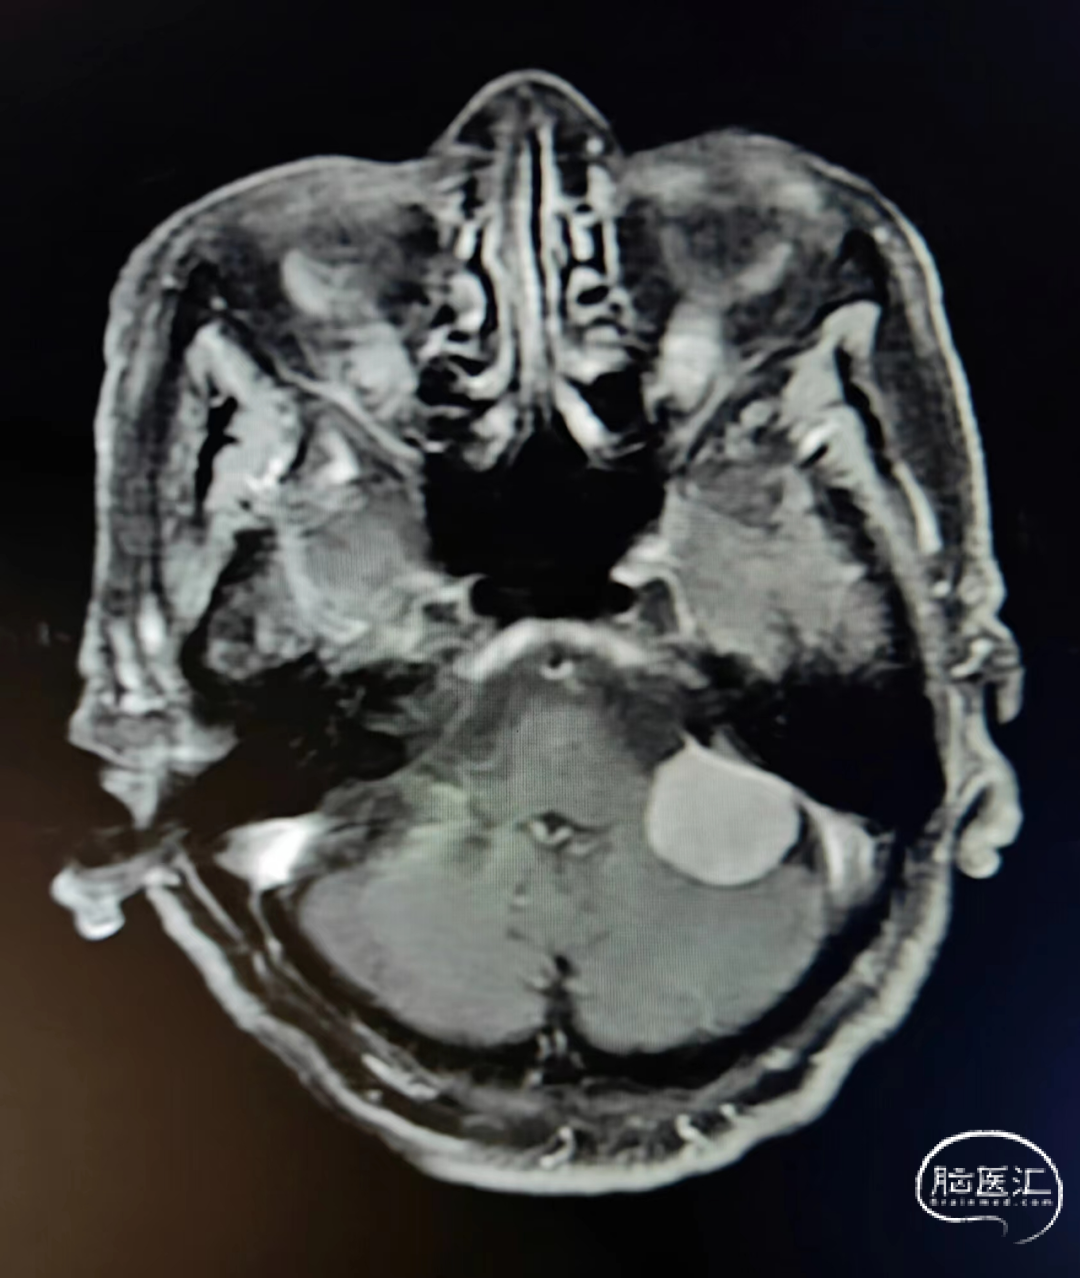

术前核磁示:左侧桥小脑角区脑膜瘤。

初步诊断:左侧桥小脑角区脑膜瘤。